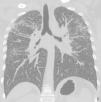

Caso 2Varón, 50 años, no fumador. Trabaja desde 1981 en la misma empresa que el caso 1, con funciones similares. Desde el año 2000 ha usado de forma habitual conglomerados artificiales de cuarzo para las superficies de cocina y baño. El paciente estaba asintomático y con actividad pulmonar normal. Se realizaron dos radiografías torácicas: una en 2011 durante la revisión médica rutinaria de la empresa y otra en 2013 (fig. 1). En 2011, según la clasificación de la OIT, presentaba opacidades nodulares de tamaño q/p con profusión 2/2 en ambos pulmones, en especial, en las regiones superiores y media. En 2011, la TAC pulmonar de alta resolución según la clasificación ICOERD mostró la prevalencia de opacidad redonda bien definida de grado 2, tamaño q predominante y profusión pulmonar suma 10 (fig. 2). Al paciente se le asignaron otras funciones para evitar que siguiera expuesto, pero en 2013, las anomalías radiográficas según la clasificación de la OIT habían aumentado (opacidades de tamaño q/r con profusión 2/3 en ambos pulmones y grandes opacidades categoría A). Las detecciones de ANA y anti-ENA correspondieron a valores normales. La prueba de quantiferón para Mycobacterium tuberculosis dio negativo. La detección de micobacteria (con microscopia directa, cultivo y PCR) y los cultivos bacterianos o micológicos en el L-LBA fueron negativos. En el hemograma se observó linfocitosis (41%) con cociente CD4+/CD8+ reducido.